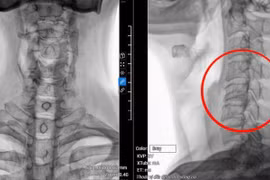

(khoahocdoisong.vn) - BV TƯQĐ 108 tiếp nhận và điều trị cho bệnh nhân N.V.T, 55 tuổi (Hà Nội) nhập viện trong tình trạng chấn thương cột sống cổ, gãy đốt sống C1 do nhảy bể bơi, không để ý mực nước trong bể bơi còn bao nhiêu.